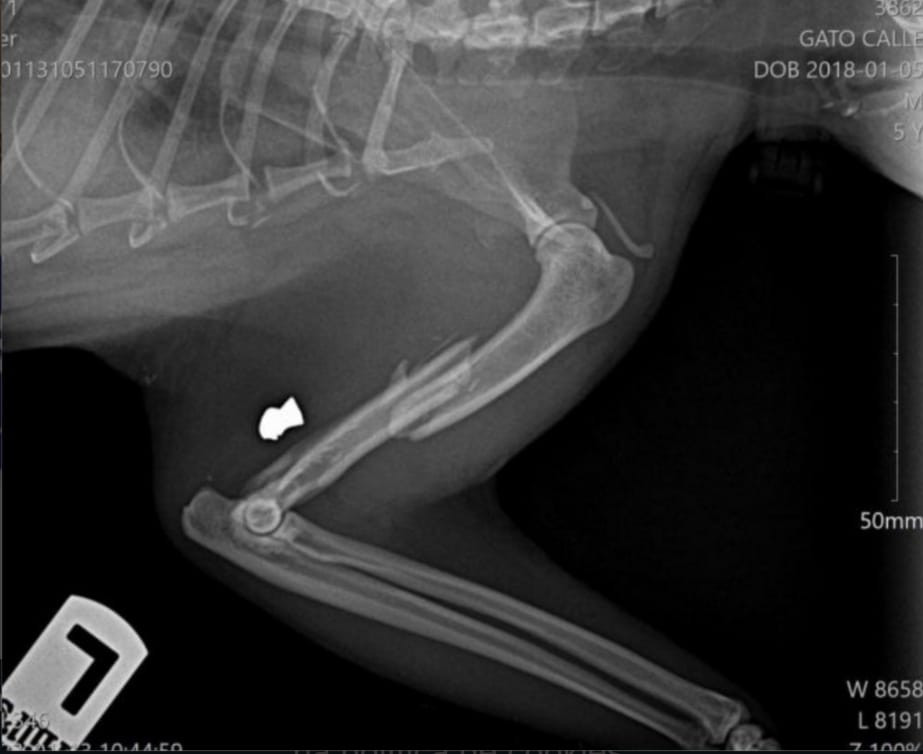

La bala le perforó el húmero y quedó incrustada. La Policía Local busca ahora al autor de los hechos y pide la colaboración ciudadana

El gató no mejoró, por lo que sus adoptantes decidieron llevarlo al veterinario. El profesional confirmó que había recibido un tiro y que la bala le había perforado el húmero, quedando incrustada en el hueso y creándole una grave lesión.

Radiografía del balazo a Lin (Policía Local de Poio).